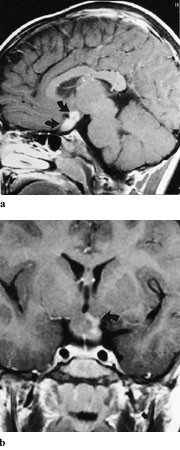

CT er mindre sensitivt ved nevritt, men kan vise fortykkede nerver, eventuelt med kontrastoppladning. Funnet kan være vanskelig å vurdere. Diagnosen av optikusnevritt kan ved MR dels baseres på volumøkning, i tillegg er økt signalintensitet i synsnerven på T2-vektede bilder eller kontrastoppladning på T1-vektet bilde karakteristisk (fig 4). Bruk av fettsuppresjon med såkalt ”short time inversion recovery” (STIR) og ved ”frequency spesific selective partial inversion recovery” (SPIR) øker den diagnostiske sensitiviteten av MR fordi nerven bedre skilles fra omgivende fettvev og fordi patologiske signalendringer derfor lettere kan sees (2). Bruk av kontrast kan gi noe varierende signalendring ved bruk av STIR, mens SPIR tryggere kan kombineres med kontrast (3). Bruk av FLAIR (fluid attenuated inversion recovery) (4) kan vise signaløkning i området med betennelse. Lesjonens utbredelse og varighet er avgjørende for graden av normalisering av visus. Gadoliniumkontrast vil tydelig vise blod-hjerne-barriere-skade i form av oppladning, eventuelle før kliniske symptomer oppstår. Dette sees både ved demyeliniserende, vaskulær eller stråleindusert optikusnevritt (5). Utvidede subaraknoidalrom er viktige tilleggstegn ved nevritt og kan fremstilles i så vel aksiale som koronale MR-snitt.